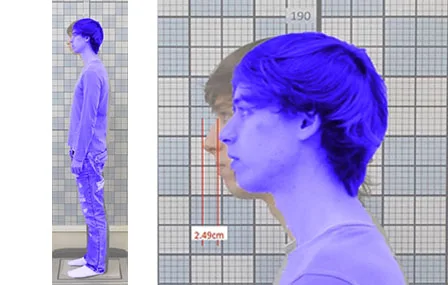

Impact de la chirurgie orthognatique - Approche interdisciplinaire

Auteurs : Robert Frey, Evgeny Gladilin, Dimitris Patikas, Pierre Bouletreau Concepts et mots clés Il est suggéré que la constriction…

Lire la suite →